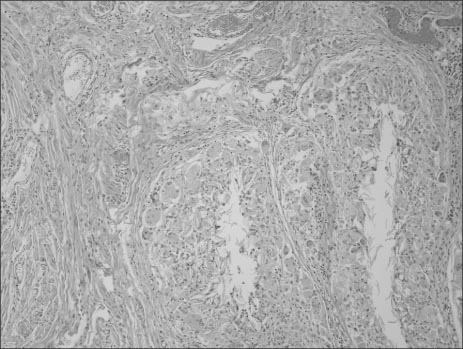

Fig. 5

Some part shows the granulomatous foreign body reaction (H&E, ×100).

Fig. 5 Some part shows the granulomatous foreign body reaction (H&E, ×100).